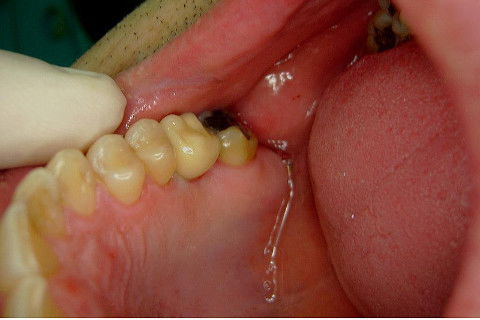

Instalação de um implante em região do 26. Utilizamos um implante cone morse Alvim Neodent 4.3 X 11,5. Foi uma cirurgia muito rápída e minimamente traumática, sem retalho e sutura.

Fotos do caso